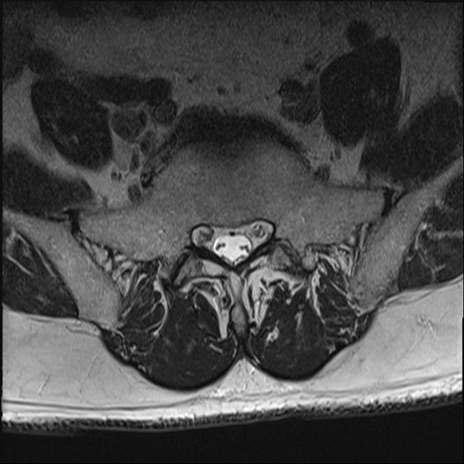

【整形】TIPS症例2 腰椎MRI T2WI(横断像)

【症例】70歳代男性

【主訴】左下肢痛

【現病歴】2週間前くらいから腰痛、左下肢痛あり。左臀部から大腿、下腿外側のしびれが常時ある。歩行とともに同部位の痛みあり。

【身体所見】Lasegue70-/60+、Bragard-/±、PTR ±/±、ATR -/-、IP 5/5、TA 5/4、TS 5/5、EHL 右第1足趾なし/3、FHL 5/5、hypersthesia(-)、足背動脈触知良好

異常所見と診断は?